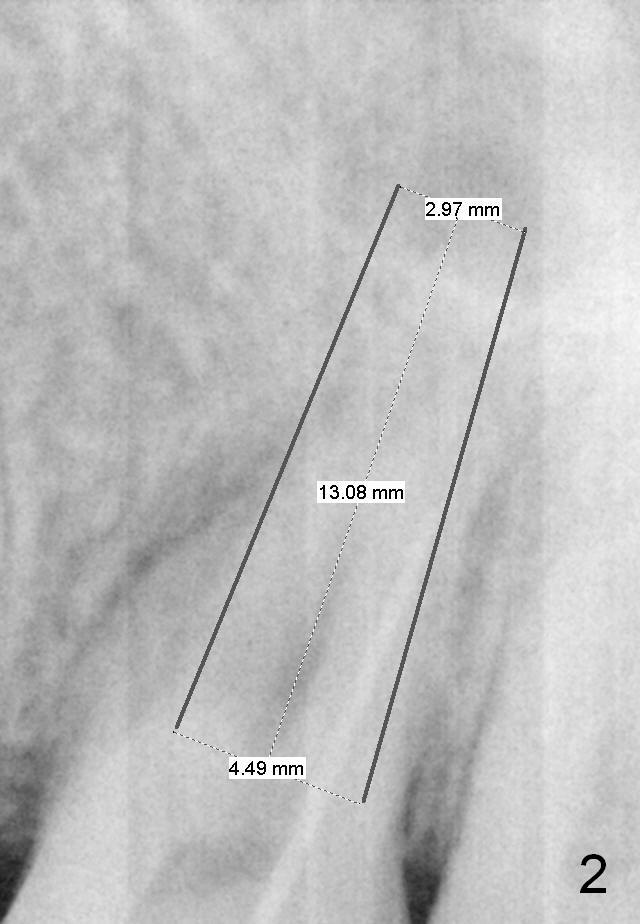

A 46-year-old woman has apical periodontitis with distal crack line at #14. There are 2 fistulae (buccal and palatal). A gutta percha is inserted into the buccal one (Fig.1 <). After extraction and Xylocaine gauze application in the socket, use 1.6 mm pilot drill in the septum for 7 mm, followed by Magic split and expanders for sinus lift. Place a relatively small implant (IBS, 4.5x13 or 5x11 mm, Fig.2) in the septum or a large one (6x13 mm or 6 mm 1-piece one, Fig.3) to obliterate the whole socket.